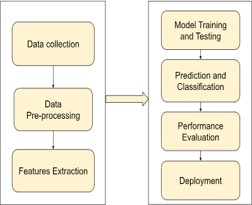

Block diagram

The figure 2 shows the DL workflow which comprises of the data collection followed by the pre-processing techniques and feature extraction. The pre-processed dataset is splitted and the model training is done [10]. The trained model is used for model validation and prediction. DL algorithms like ResNet-169, EfficientNetB2, CNN algorithm is utilized for the model classification and finally for the performance evaluation is done and deployment takes place.